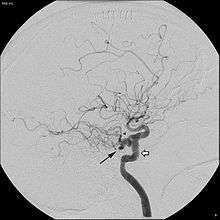

In around 0.1 to 0.6% of individuals, as sampled by magnetic resonance angiography, the trigeminal artery fails to involute and remains in the adult brain, in a condition called persistent trigeminal artery.[3] This condition is more common in women than in men, with approximately 1.8 times as many women having the condition.[6] Knowledge of a persistent trigeminal artery may be important in certain brain surgeries, as the condition is rare and an accidental cut to the artery could lead to hemorrhage.[1] Although the discovery of a persistent trigeminal artery is sometimes an incidental finding, its presence is also associated with various pathological conditions, and must therefore be considered carefully when diagnosing these conditions.[7]

A persistent trigeminal artery is associated with an increased risk of aneurysm, though some studies have suggested that this finding may be an effect of selection bias, as most individuals do not undergo the tests necessary to identify the condition.[3] Persistent trigeminal artery has been identified as a rare cause of trigeminal neuralgia, with 2.2% prevalence of persistent trigeminal artery among trigeminal neuralgia patients.[8] Surgery to move the persistent trigeminal artery away from the trigeminal nerve has been successful in treating the trigeminal neuralgia in some cases.[9] In some cases, presence of a persistent trigeminal artery concurs with hypoplasia of the basilar artery, in which case the internal carotid artery is responsible for most blood flow to the upper pons, cerebellum, midbrain, and parts of the temporal and occipital lobes, meaning that anything disrupting blood flow in the internal carotid artery could lead to ischemia in these regions.[10] In addition, persistent trigeminal artery has been associated with vertebrobasilar insufficiency, brainstem ischemia, and carotid cavernous fistulae.[2]